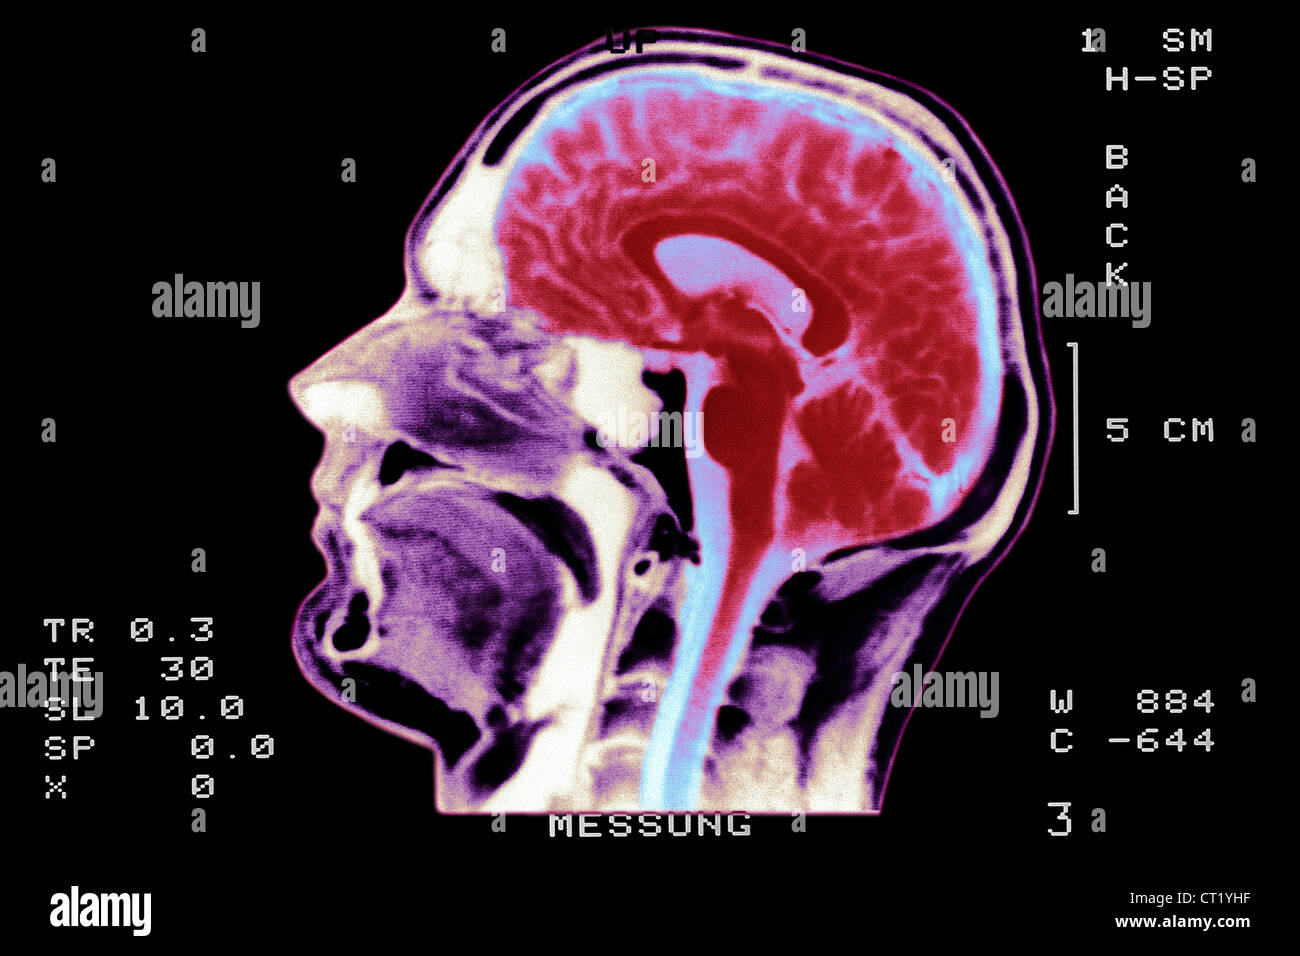

Brain scan Stock Image C012/9754 Science Photo Library How Do I Know If I Need A Brain Scan How to cope with the mri experience. Learning that you need to undergo a magnetic resonance imaging (mri) test can be intimidating. the term “brain scan” can refer to an mri scan, ct scan, and pet scans or a combination. A brain aneurysm is a weak, bulging area in the wall of an artery in your brain. a. How Do I Know If I Need A Brain Scan.

Coloured MRI brain scan, back view Stock Photo 60882847 Alamy How Do I Know If I Need A Brain Scan table of contents. Brain scans may help evaluate head injuries,. a brain ct scan visualizes the structure of the brain and skull, and it can identify blood in and around the brain. A brain ct scan can also identify fluid, swelling, large tumors, or a large stroke. the term “brain scan” can refer to an mri scan,. How Do I Know If I Need A Brain Scan.